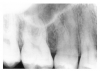

Figure 1 is a molar bitewing radiographic image that discloses a defective abutment restoration on tooth #4. The restoration ends short leaving open margins.

Figure 1 - Defective Restoration; Abutment Tooth #4

Figure 1